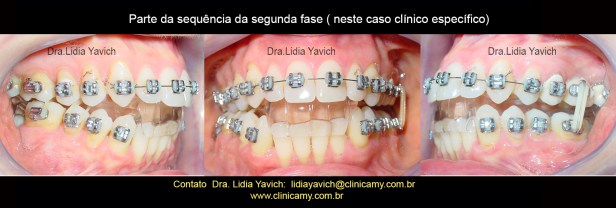

Foi decidido iniciar a SEGUNDA FASE do tratamento para retirar o DIO (dispositivo intraoral), mantendo a oclusão neuromuscular fisiológica.

Para isso utilizamos uma ortodontia tridimensional, onde os dentes são erupcionados para a nova posição neurofisiológica.

Na segunda fase, neste caso a ortodontia tridimensional a paciente é monitorada e desprogramada eletronicamente, e muitas vezes o dispositivo é recalibrado, para manter a posição obtida na primeira fase.

Na segunda fase, neste caso a ortodontia tridimensional a paciente é monitorada e desprogramada eletronicamente, e muitas vezes o dispositivo é recalibrado, para manter a posição obtida na primeira fase.

Parte da sequência da segunda fase (neste caso clínico específico).

Parte da sequência da segunda fase (neste caso clínico específico).

Parte da sequência da segunda fase (neste caso clínico específico).

Parte da sequência da segunda fase (neste caso clínico específico).

Parte da sequência da segunda fase (neste caso clínico específico).

Parte da sequência da segunda fase (neste caso clínico específico).

Parte da sequência da segunda fase (neste caso clínico específico).

Parte da sequência da segunda fase (neste caso clínico específico).

Parte da sequência da segunda fase (neste caso clínico específico).

Parte da sequência da segunda fase (neste caso clínico específico). Fotografia do fio ortodôntico antes de cortar do lado direito para fins didáticos.

Parte da sequência da segunda fase (neste caso clínico específico). Fotografia do fio ortodôntico antes de cortar do lado direito para fins didáticos.

Parte da sequência da segunda fase (neste caso clínico específico).

Parte da sequência da segunda fase (neste caso clínico específico).

Parte da sequência da segunda fase (neste caso clínico específico).

Parte da sequência da segunda fase (neste caso clínico específico).

Parte da sequência da segunda fase (neste caso clínico específico).

Parte da sequência da segunda fase (neste caso clínico específico).

Parte da sequência da segunda fase (neste caso clínico específico).

Parte da sequência da segunda fase (neste caso clínico específico).

Parte da sequência da segunda fase (neste caso clínico específico).

Parte da sequência da segunda fase (neste caso clínico específico).

Parte da sequência da segunda fase (neste caso clínico específico).

Parte da sequência da segunda fase (neste caso clínico específico).

Retirada do DIO ( dispositivo intraoral)

Parte da sequência da segunda fase (neste caso clínico específico).

Parte da sequência da segunda fase (neste caso clínico específico).